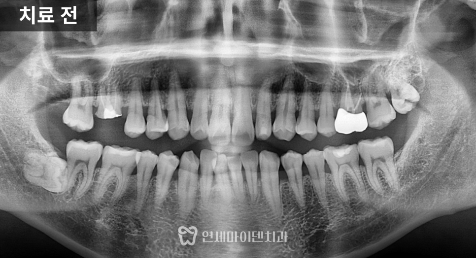

이 케이스 역시 과거에

신경치료 후 크라운 치료를

받은 어금니였습니다.

중요한 점은

뿌리 끝 염증이 없었다는 점,

뼈 레벨 위쪽으로 본인 치아가

일부 남아 있었다는 점입니다.

하지만 이 케이스에서는

잇몸뼈 위쪽에 약 3~4mm 이상의

자연 치아가 남아 있는 상태였습니다.